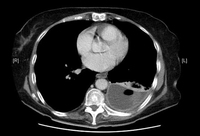

CT scan of thoracic empyema

From the collection of Najib Rahman, RTU, Oxford